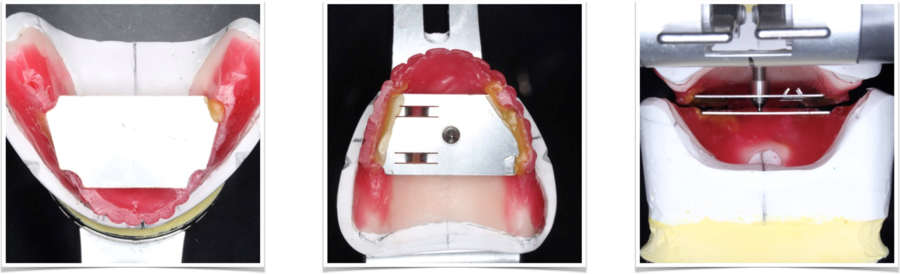

人工歯配列試適

ピエゾグラフィーを参考にして配列した歯を元に上顎の歯もろうそくのワックスを用いて歯を並べたものを、お口の中に入れて見た目やかみ合わせをチェックします。

治療用義歯完成(保険)

治療用義歯の完成になります。上下左右ともにしっかりと噛んでいます。お口の中に入れてかみ合わせを調整して、セットしました。

この患者さんの治療用入れ歯(義歯)は、保険で作製しています。治療用入れ歯(義歯)は、多くの場合、保険で製作します。